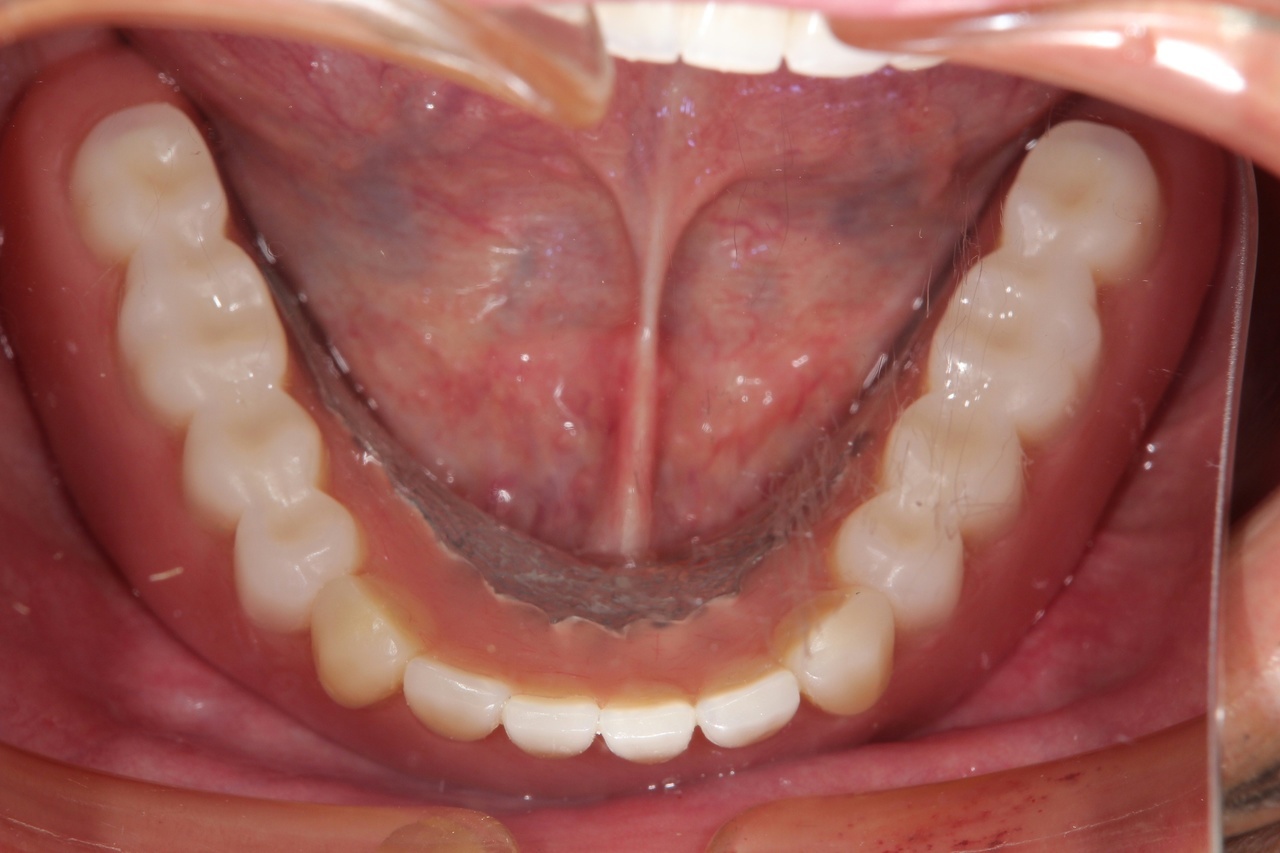

歯周病とインプラント(抜歯即時荷重)<ガイドシステムを使用した埋入法>

インプラント8本で14本の歯を並べたケース・仮歯代含む (函南町在住 女性

抜歯後、片顎8本のインプラントを埋入し、即日に仮歯を製作する事により、1日で片顎14本の歯を回復します。事前にインプラントを埋入する位置をCTによりシミュレーションし、埋入ガイド、仮歯を準備したうえで手術を行います。埋入ガイドにより、正確な位置にインプラントを埋入することができます。

治療の流れ

治療前

下の歯は歯周病でグラグラです。

後のインプラント手術時に、抜歯します。